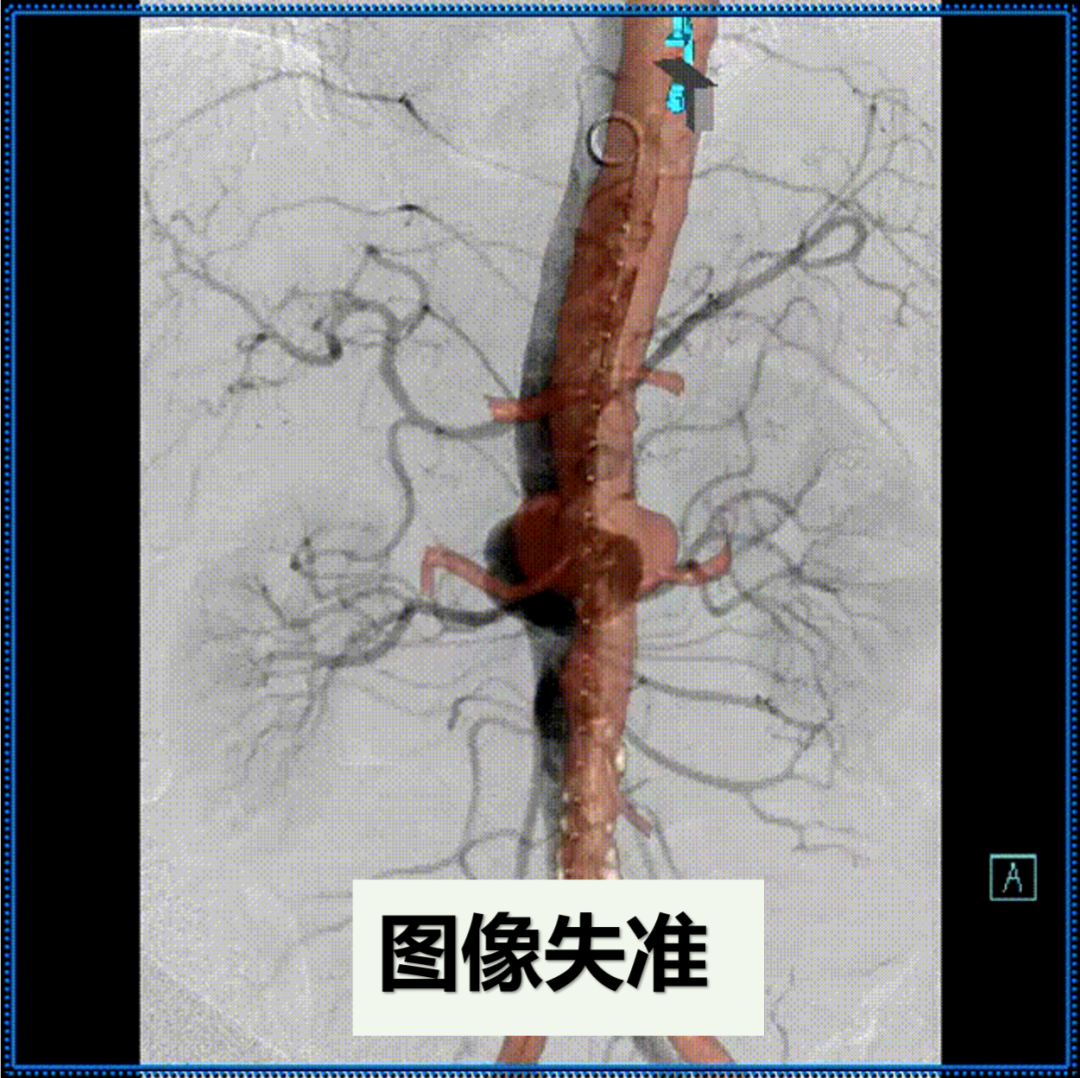

影像配准:根据术中实时影像对3D影像进行必要的微调校正。

3D影像融合

术中3D影像引导,主体支架精准定位

3D影像引导下,

主体支架窗口与弓上三分支开口对位